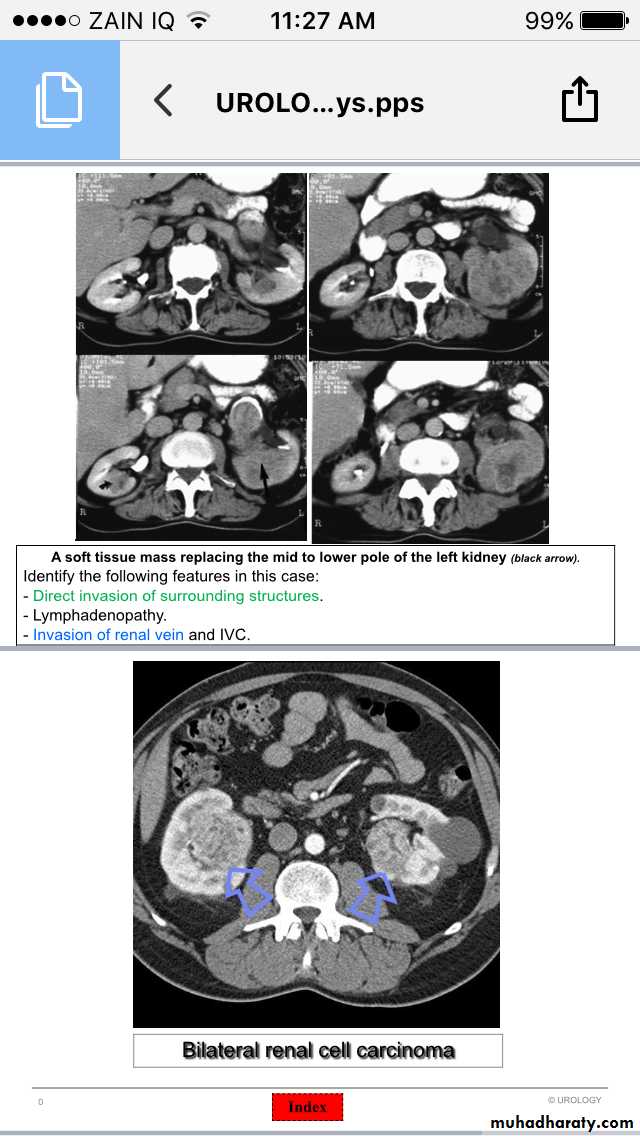

Renal Neoplasms